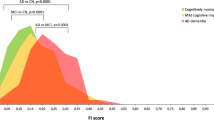

Topography and extent of neurodegeneration in education-based subgroups

When compared with CTR, all education-based subgroups were characterized by hypometabolism in AD-typical posterior parietal regions of both hemispheres. In particular, as expected, in the Low-EDUC and Average-EDUC subgroups, hypometabolism was restricted to the left posterior parietal and middle temporal cortices (BAs 40 and 38), whereas the High-EDUC subgroup demonstrated a more extended hypometabolism in the left superior temporal and posterior cingulate cortices, in the right fusiform gyrus, and in the posterior parietal cortex and precuneus in both hemispheres (BAs 7, 20, 22, 30, 31, and 40). When compared with CTR, the Except-EDUC subgroup showed a cluster of significant hypometabolism including the left posterior parietal cortex (larger with respect to Low- and Average-EDUC subgroups but not further extended with respect to High-EDUC subgroup). See Fig. 4 and Table 6 for further details.

Cortical hypometabolism in education-based subgroups with respect to healthy volunteer control subjects (CTR). The whole patient group (n = 133) was divided into quartiles to obtain education-based subgroups: poorly educated (first quartile; Low-EDUC), average education level (second quartile; Average-EDUC), highly educated (High-EDUC; third quartile), and exceptionally educated (fourth quartile; Except-EDUC). All education-based subgroups were characterized by hypometabolism in Alzheimer’s disease-typical cortical regions with respect to CTR. However, the High-EDUC subgroup demonstrated a more extended hypometabolism (than the Low-Educ and Average-EDUC subgroups) involving a more extended hypometabolism in the left superior temporal and posterior cingulate cortices, in the right fusiform gyrus, and in the posterior parietal cortex and precuneus in both hemispheres. The Except-EDUC subgroup showed a cluster of significant hypometabolism including only the left posterior parietal cortex (larger with respect to Low- and Average-EDUC subgroups but not further extended with respect to the High-EDUC subgroup). See Table 6 for details on coordinates and z-scores. Other details are the same as in the Fig. 2 legend